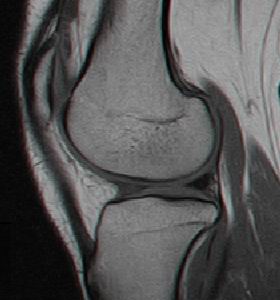

1.2.3. Rezonanta Magnetica Nucleara

Secventele standard T1 fast-spin nu sint sensibile in evaluarea leziunilor cartilajului articular, insa secventele T2 fast-spin si T1 densitate protonica cu supresie a grasimii sint atit specifice cit si senzitive in decelarea leziunilor cartilajului articular (fig. 1.5) Cea mai mare specificitate este la nivelul cartilajului articulatiei femuropatelare datorita grosimii cartilajului (fig. 1.6)

In Figura 1.9 si Figura 1.10 se pot observa leziuni de osteocondrita disecanta a condilului femural intern si extern, evidentiabile pe diferite sectiuni si secvente RMN.

Fig1.9 Imagine RMN sectiuni sagitale si transversala la nivelul genunchiului, leziune de osteocondrita disecanta a condilului femural intern |

Fig. 1.11 Imagine RMN, sectiune sagitala la nivelul compartimentului intern al genunchiului drept, genunhi in extensie |